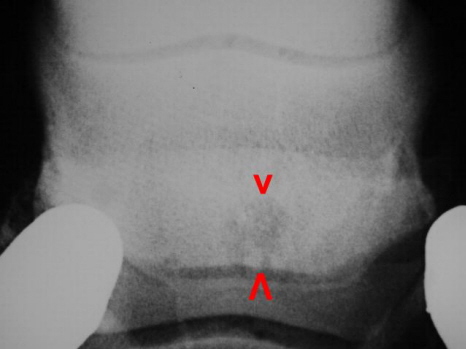

Hufrolle Zyste